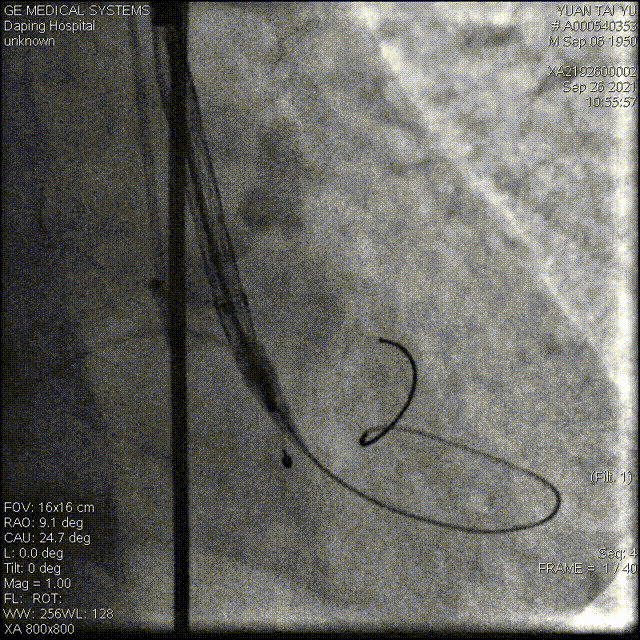

高位释放瓣膜

受钙化挤压影响,瓣膜展开状态差,决定进行后扩

22mm球囊后扩

经后扩,支架展开形态良好